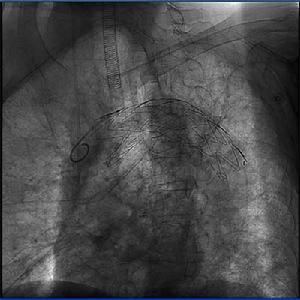

1、胸部X線檢查及計算機斷層攝片檢查可顯示動脈瘤塊影並可能見到搏動或血栓。2、主動脈造影可明確診斷並顯示動脈瘤的部位、形態和範圍。但因其有創傷,可能引起周圍動脈栓塞等併發症而使套用受到限制。